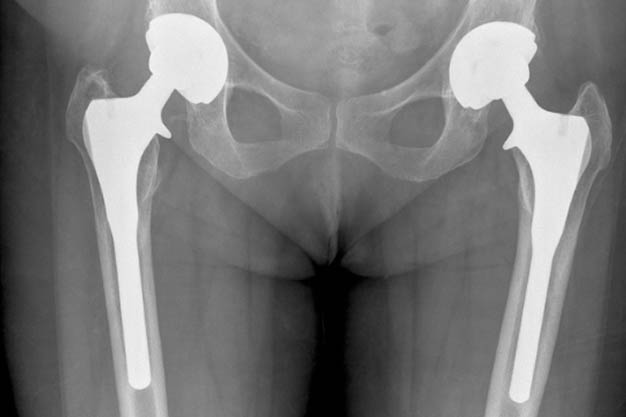

Do I Need a Joint Replacement?

Before answering the question, "Do you need joint replacement?", you first need to learn the facts needed for the joint replacement process. Let's start by establishing some basics. Many joints in the body, such as wrists, ankles, shoulders, and elbows, can be replaced with artificial joints. On the other hand, knee and hip prostheses are the most common.